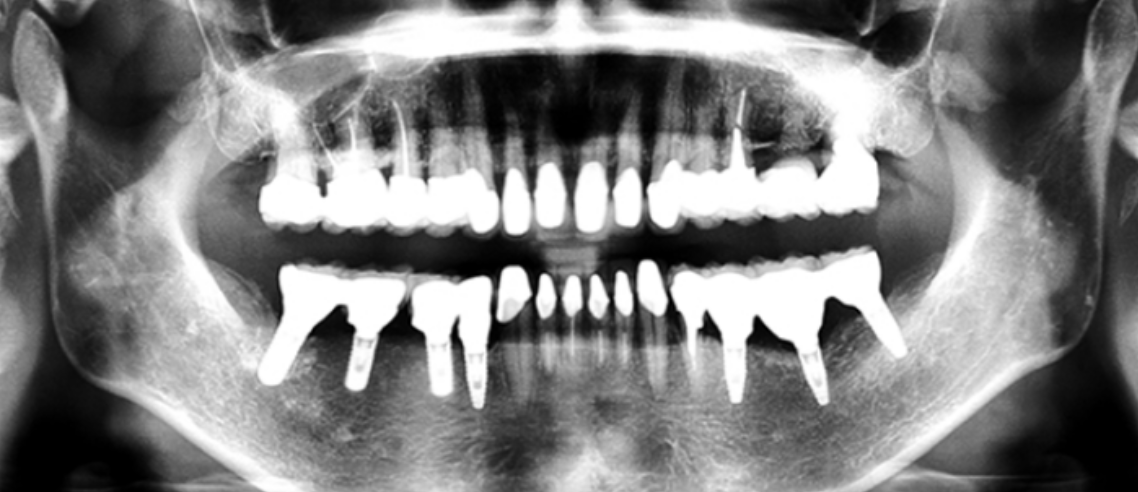

下の奥歯が左右なくなっており、かみ合わせが深くなっています。

顎のずれは認めませんが、歯肉が厚く中に炎症を取りこみやすいタイプの歯肉です。

左の顎の骨が大きく溶けてなくなっております。

かみ合わせの深さを改善し、左下の骨を作り人工歯根で再構築しました。

前歯は、患者さんの希望でフルセラミックで対応しました。